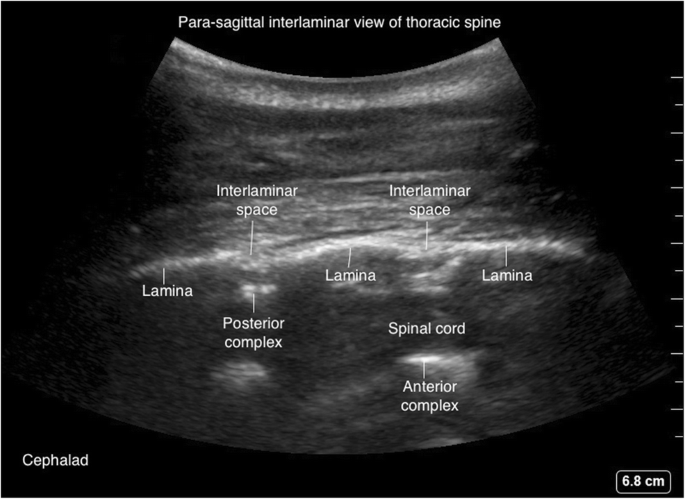

Thoracic spine

The upper thoracic (T1-T4) and lower thoracic (T9-12) vertebrae have similar geometry to cervical and lumbar vertebrae and amenable for US scanning (Fig. 19). The mid-thoracic (T5–T8) vertebrae have extreme inferior angulation of spinous process and pose technical challenges for ultrasound scanning (Fig. 20).

The para-sagittal windows can be obtained by beginning laterally with identification of ribs and pleura, then moving medially with identification of transverse process, articular process, and lamina. The para-sagittal interlaminar view (Figs. 21 and 22) is used to locate the interlaminar space as a marking point for the neuraxial procedure. The transverse views (Figs. 23 and 24) are challenging to obtain in the mid-thoracic spine as the transverse interspinous windows are narrow here. The presence of a rib marks the junction of the T12 and L1 vertebra. The 12th rib can be identified to locate the T12 vertebra, and the counting-down approach can be used to locate accurate lumbar intervertebral levels, or the counting-up approach can be used to locate the correct thoracic intervertebral level. Alternatively, the correct level can be determined by counting down from the T1 level, after locating the first rib.

파라사갈리탈 창은 늑골과 흉막을 식별하며 측방에서 시작하여, 가로 과정, 관절 과정, 및 층판을 식별하며 내측으로 이동하여 얻을 수 있습니다. 파라사갈리탈 간층판 관점(그림 21 및 22)은 신경축 수술의 표시점으로 간층판 공간을 위치시키는 데 사용됩니다. 횡단면(그림 23 및 24)은 흉추 중간 부위에서 횡간돌기 간 창이 좁기 때문에 획득이 어렵습니다. 늑골의 존재는 T12와 L1 척추체의 접합부를 표시합니다. 12번째 늑골을 식별하여 T12 척추를 위치시키고, 하향 계수 방법을 사용하여 정확한 요추 간 척추 수준을 찾거나, 상향 계수 방법을 사용하여 정확한 흉추 간 척추 수준을 찾을 수 있습니다. 또는 첫 번째 늑골을 위치시킨 후 T1 수준에서 하향 계수하여 정확한 수준을 결정할 수 있습니다.

Para-sagittal interlaminar (oblique) view of thoracic spine